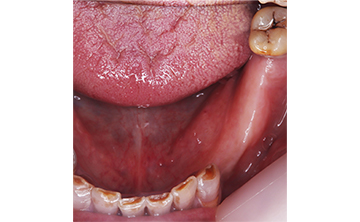

虫歯を放置して3年経って来院された患者さんです。噛めなくなったが主訴です。虫歯が進行しているのも確かですが、歯石も多く付着していますね。虫歯の中にオレンジのものが見えていますが、これは、根の治療後に詰める防腐剤ですね。

根の治療をすると歯に痛みを感じなくなるので、虫歯が進行しても痛みを感じずに歯冠崩壊を招きます。できるだけ歯の神経を取らない方が良いですが、虫歯が歯の神経に近く痛みが出る場合は、虫歯の歯の神経治療が必要になります。